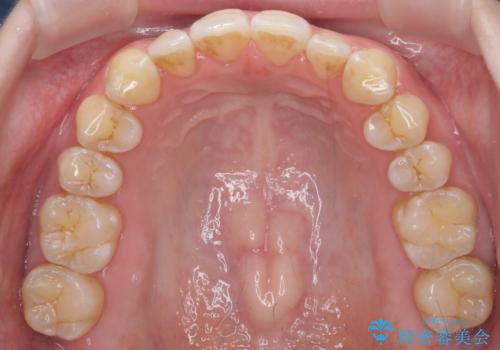

前歯のガタつき インビザラインで 下の前歯を1本抜歯

- 前歯のがたつきを主訴に来院。マウスピース矯正を希望されました。

治療にあたり、下の前歯を一本抜歯しています。

非抜歯で無理に治療をしようとすると、下の前歯の骨が薄く歯ぐきが下がったり、歯がぐらついたり、がたつきが完全にとれないリスクがあることを説明しました。

下の前歯が3本になるため、上下の正中は合わない仕上がりとなりますが、正中を合わせるには上下左右4本抜歯の上、ワイヤー矯正となってしまいます。

それよりは抜歯の数も少なく、メリットが大きいのではないかと説明し、選んでいただきました。

短期間できれいな歯並びになり、大変満足していただきました。